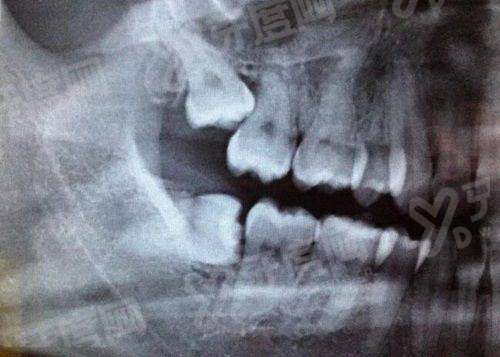

①数字化种植牙技术:在种植前,和传统种植牙技术相比医生就可借助通过3D扫描、CAD辅助设计进行建模,可以为患者在种植的时候避开重要的神经血管结构,摆脱传统种植牙不需要切开牙龈,翻瓣、缝合、拆线等步骤,患者种植舒适度高。

③3D微创0痛种植牙技术:在上海曙康口腔医院种植牙是可以通过院内数字化设备,对患者顾客设计个性化定制种植方案,进行可视化种牙,拒绝盲种,且种植约15分钟就可以种好,各个种植品牌都是可种植的、